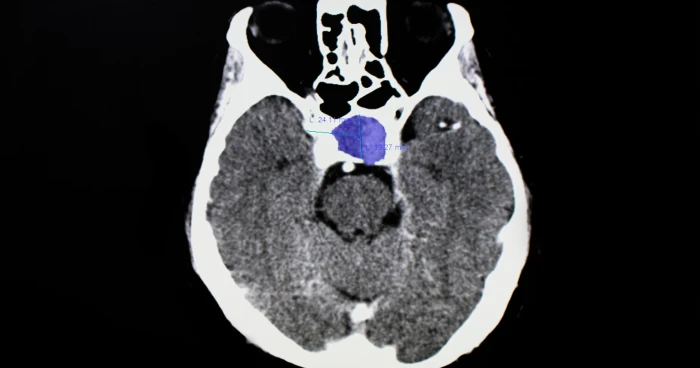

Diagnoza bëhet zakonisht me analiza hormonale, CT ose rezonancë magnetike. Trajtimi varet nga madhësia e tumorit, hormonet që prodhon dhe ndikimi në shikim ose në strukturat e trurit përreth. Disa tumore kërkojnë vetëm monitorim, ndërsa të tjerat trajtohen me ilaçe, kirurgji ose terapi me rrezatim.